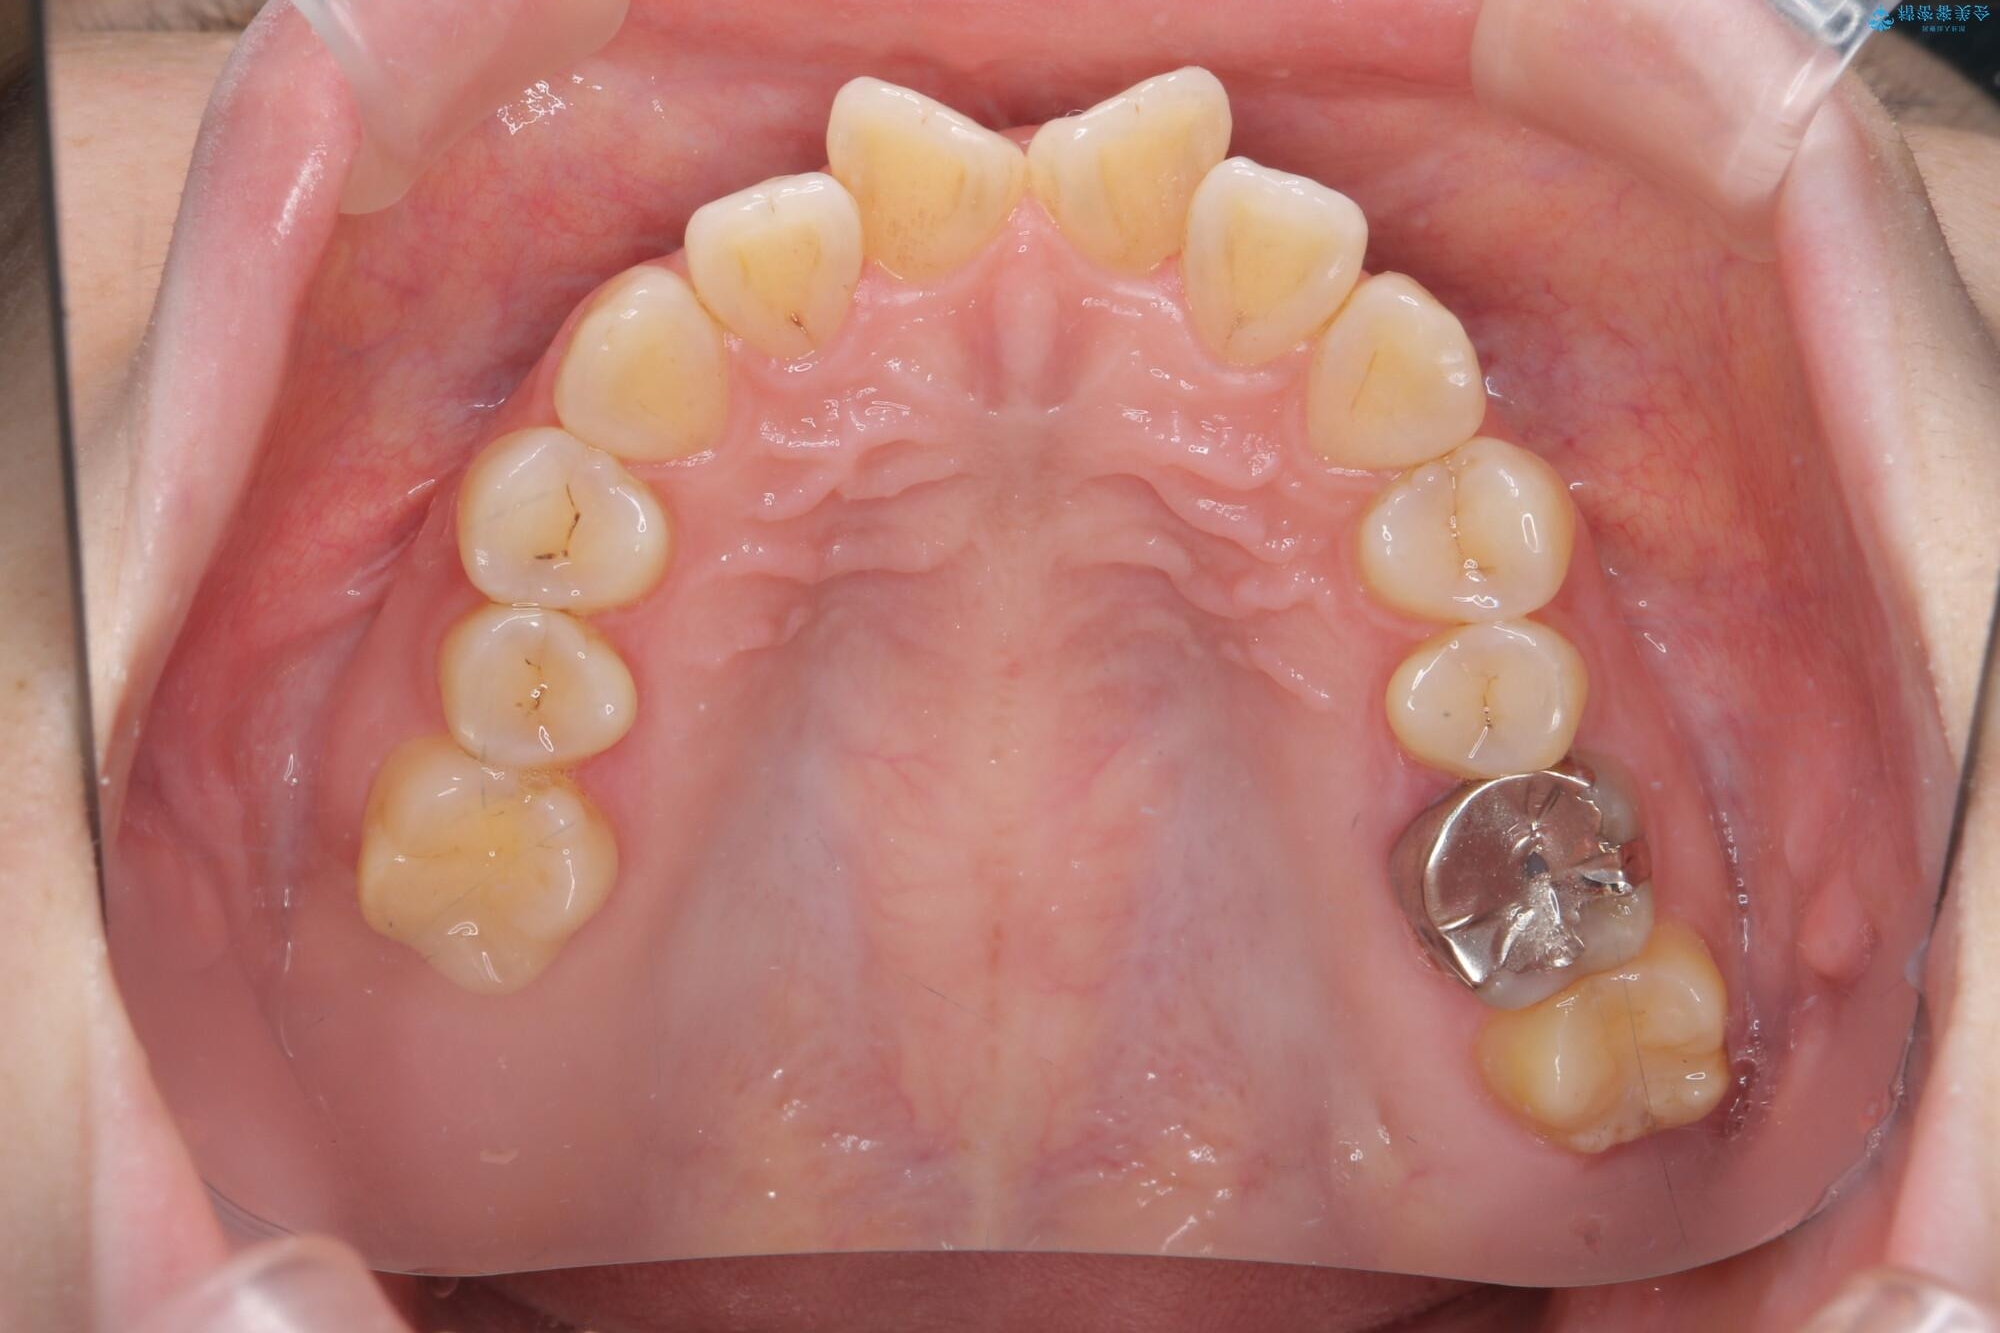

治療前

傾いた前歯、インビザラインで改善 治療前画像 傾いた前歯、インビザラインで改善 治療前画像 傾いた前歯、インビザラインで改善 治療前画像 傾いた前歯、インビザラインで改善 治療前画像